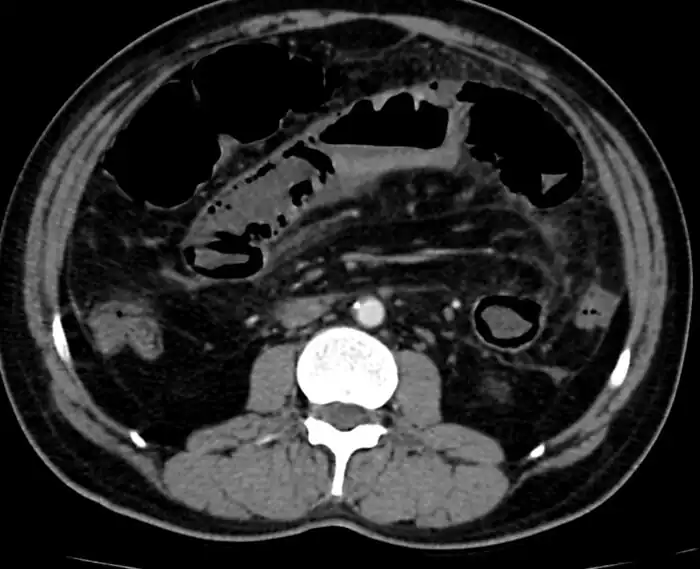

Mesenteric ischemia/CT image

Mesenteric ischemia